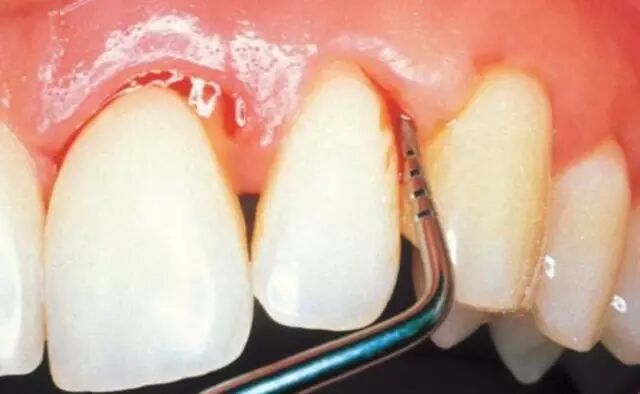

洗牙,就是处理牙结石最有效的方式,通过超声波震动震碎牙结石,达到清除牙结石减轻牙龈负担的效果。不过,简单的洗牙不能完全解决牙结石的问题,因为有些人的牙结石会长在牙龈下面,牙周袋内,常规的洗牙只能去除表面的牙结石,不能达到清洁牙齿的效果,想要彻底清除刺激物,就需要做深度清洁(深刮)。

龈下刮治

如果医生建议龈下刮治,表明你的「牙周炎」已经有点严重了。刮治可以有效清除藏在牙龈里面的牙菌斑,让牙龈紧紧贴近牙齿表面,这样牙齿才会牢固。